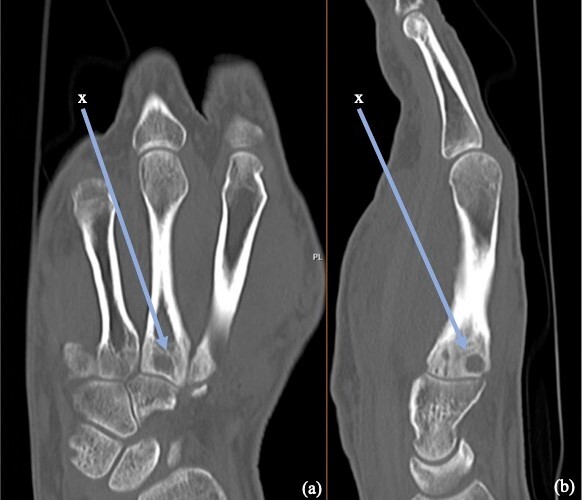

Examination revealed generalised swelling of the entire right hand with multiple small lumps on the volar surface and one sinus on the palm discharging small red grains. There was no cellulitis or tenderness present in the hand (Figure 1). He had a full range of motion and normal sensation in the hand with no lymphadenopathy. Imaging with a CT scan found cortical erosions and cystic changes at the base of the third metacarpal suggestive of osteomyelitis (Figure 2). These soft tissue lesions were shown to be multiple rim-enhancing collections within the intrinsic musculature of the hand, in keeping with infective abscesses on MRI. Imaging also showed erosion of the third metacarpal base, loculated collections around multiple carpometacarpal joints and bony inflammation.